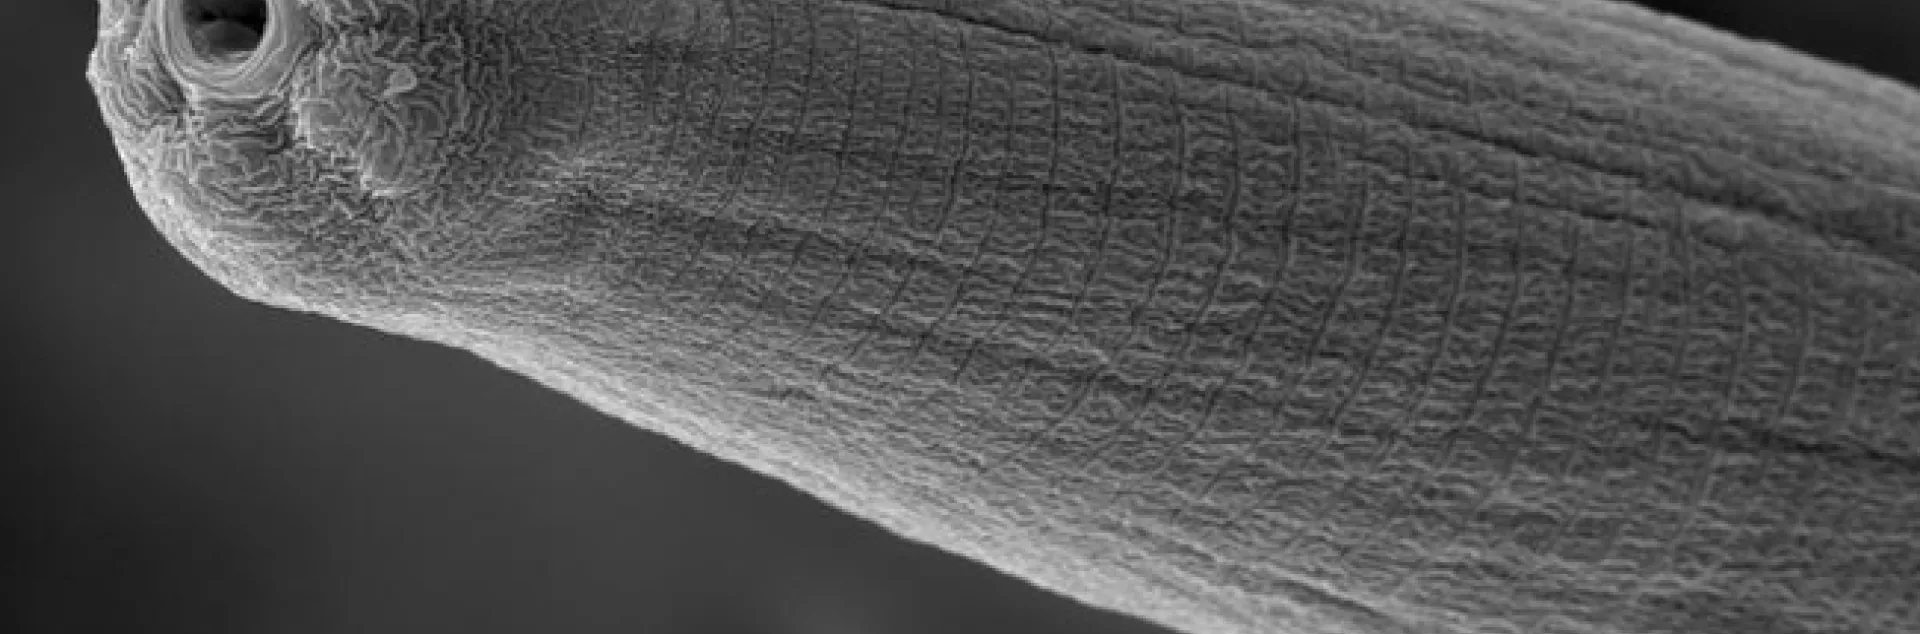

Who knew that you, along with billions of other people, could be infected with undetected microscopic parasitic nematodes, or round worms? And that they spit venom?

"Parasitic nematodes are master manipulators of host immunity," Dillman says in his abstract. "Little is known about the identity and function of the cocktail of effectors they release during active infection. We have developed an effector discovery model using entomopathogenic nematodes and fruit flies, which we are using to identify and characterize potent modulators of insect immunity."

Dillman, who joined the UC Riverside faculty in February 2015 and is now an associate professor, focuses his research on identifying the specific proteins in a nematode's spit or venom that can trick the immune system to ignore its presence. His model organism is the fruit fly. He hopes that his research could lead to treatments for autoimmune diseases in humans, such as celiac, Crohn's or inflammatory bowel diseases.

"You can have a person riddled with infection who never realized there's a 2-centimeter-long worm in their eye and thousands of parasites in their blood," Dlllman told her. "The immune system never signaled something was wrong. How is that possible? We know very little about how that works."

Devastating Parasites. Nematodes, he says, are "devastating parasites of humans, capable of modulating our biology in numerous ways, including suppressing our immune systems. The goal of my lab is to understand this modulation and to characterize the chemical pathways that allow it to happen. There's compelling data that parasites could even be used to treat autoimmune disorders such as Crohn's or inflammatory bowel disease. Parasitic worms are just the coolest things you could study because there are so many strange interactions, both positive and negative, that occur between the worms and their hosts."